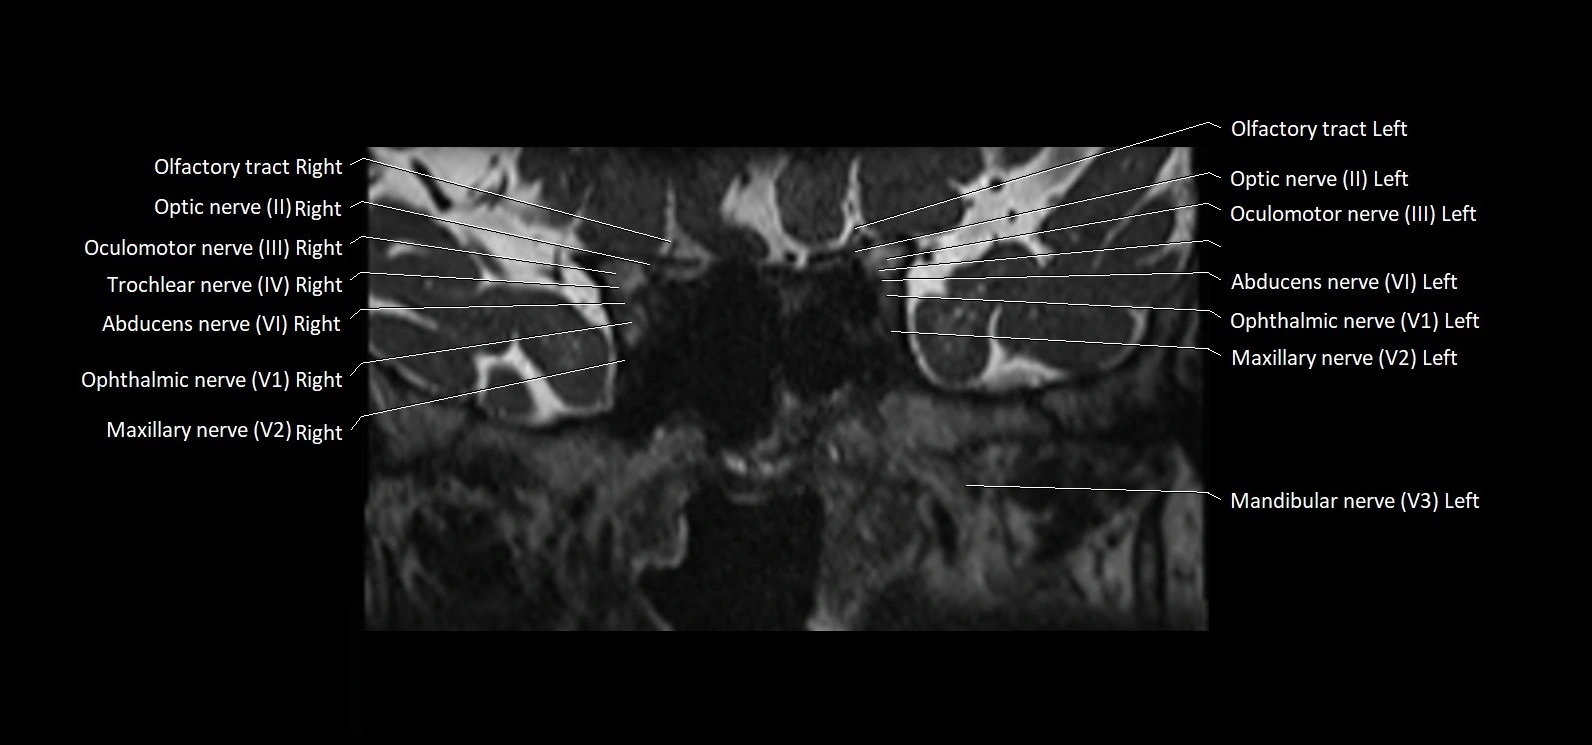

MRI images

image